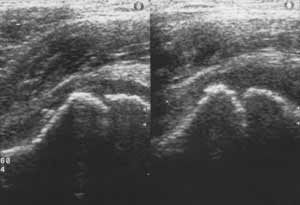

Рис. 3. Сонограммы тазобедренных суставов мальчика 4 лет с коксалгией через 6 недель после начала заболевание. Увеличение ультрасонографического суставного пространства и толщины хрящевого покрова эпифиза на стороне поражения при развивающейся начальной стадии остеохондропатии головки бедра.